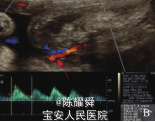

查体:一般情况可,心肺体查无明显异常,产科检查:宫高 32cm,腹围 98cm,胎心 140次/分。 孕35+2周B超:宫腔内探及一结构正常胎儿(泵血儿)及一不规则球形含骨性包块(无心畸胎儿) 。1个胎盘,两胎儿间见纤细光带分隔。无心畸胎儿固定于宫腔右下方,羊膜光带紧贴胎儿周边,大小为 9.3cm×7.0cm×5.1cm,无头、无心、无上肢,全身皮肤明显水肿,厚约 2.4cm, 内可见不规则骨性结构, 光团远端见一小肢体样结构(图1) ,腹部可见 1.5 cm 连续性中断,中断处可见 3.0 cm ×2.8 cm肿块向外膨出,内可见肠管回声。体内及脐血管内可见血流信号,脐动脉反向灌注朝向胎儿体内,脐动脉搏动指数1.06,阻力指数 0.67,收缩期 / 舒张期比值 3.0(图 2) 。